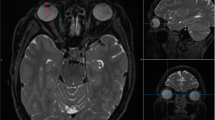

Measurements of overall eye volume and length, including the axial length and transverse length, were conducted by one certificated radiologist (Y.T.) and two trained researchers (A.F. and K.Y.). Images of each eye were separately segmented semi-manually on T2-VISTA multiplanar orthogonal slices, using an image-contour program (Amira 6.4.0, Maxnet Co., Ltd.) (Fig. 5).

Three-dimensional (3D) eyeball segmentation with Amira. (A) A representative axial reconstructed plane of 3D T2-VISTA image. Identical eyes are semi-automatically contoured by threshold method based on their signal intensity. (B) 3D volume-rendering reconstructed images of the segmentation of whole eyeballs are derived from image in (A). Left anterior oblique view (B) and right anterior oblique view (C). Yellow and purple segmentations demonstrate volume and shape of the right eyeball and the left eyeball, respectively.